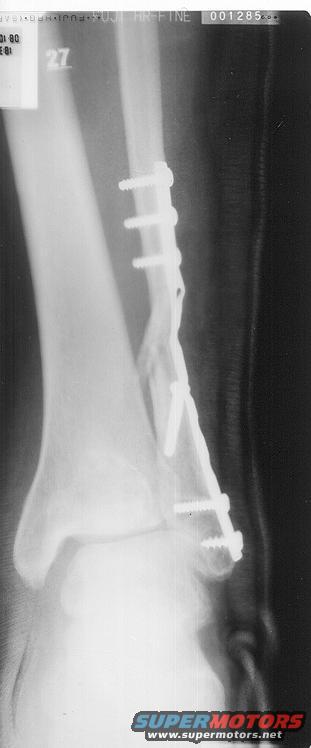

broken_leg4.jpg | Hits: 682 | Posted on: 6/30/03 |

Yet another. and the last. lol